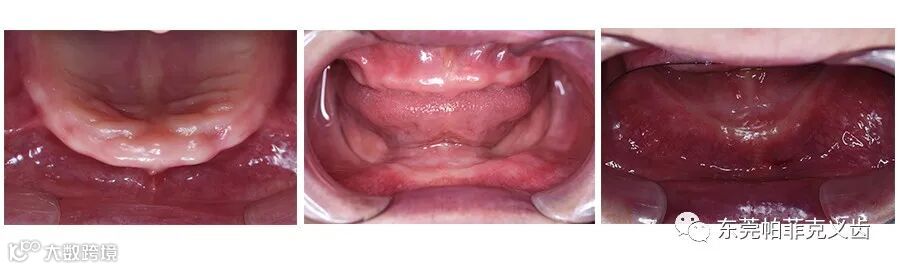

【案例展示】